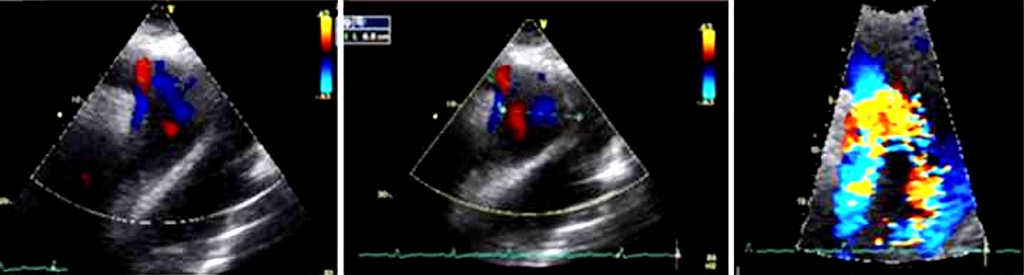

Figure 1 Axis suprasternal echocardiogram, aortic arch and descending aorta is observed, with double-lumen image.